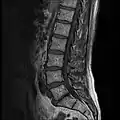

MRI